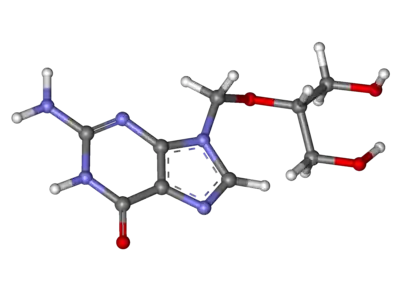

| 3D model (JSmol) | |